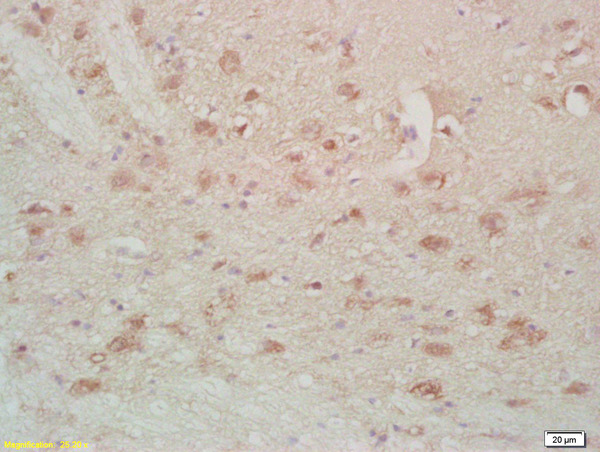

FABP7 Polyclonal Antibody

Product Name FABP7 Polyclonal Antibody

Applications ELISA, IHC-P, IHC-F, IF(IHC-P), IF(IHC-F), IF(ICC)

IHC-P 1:200-400